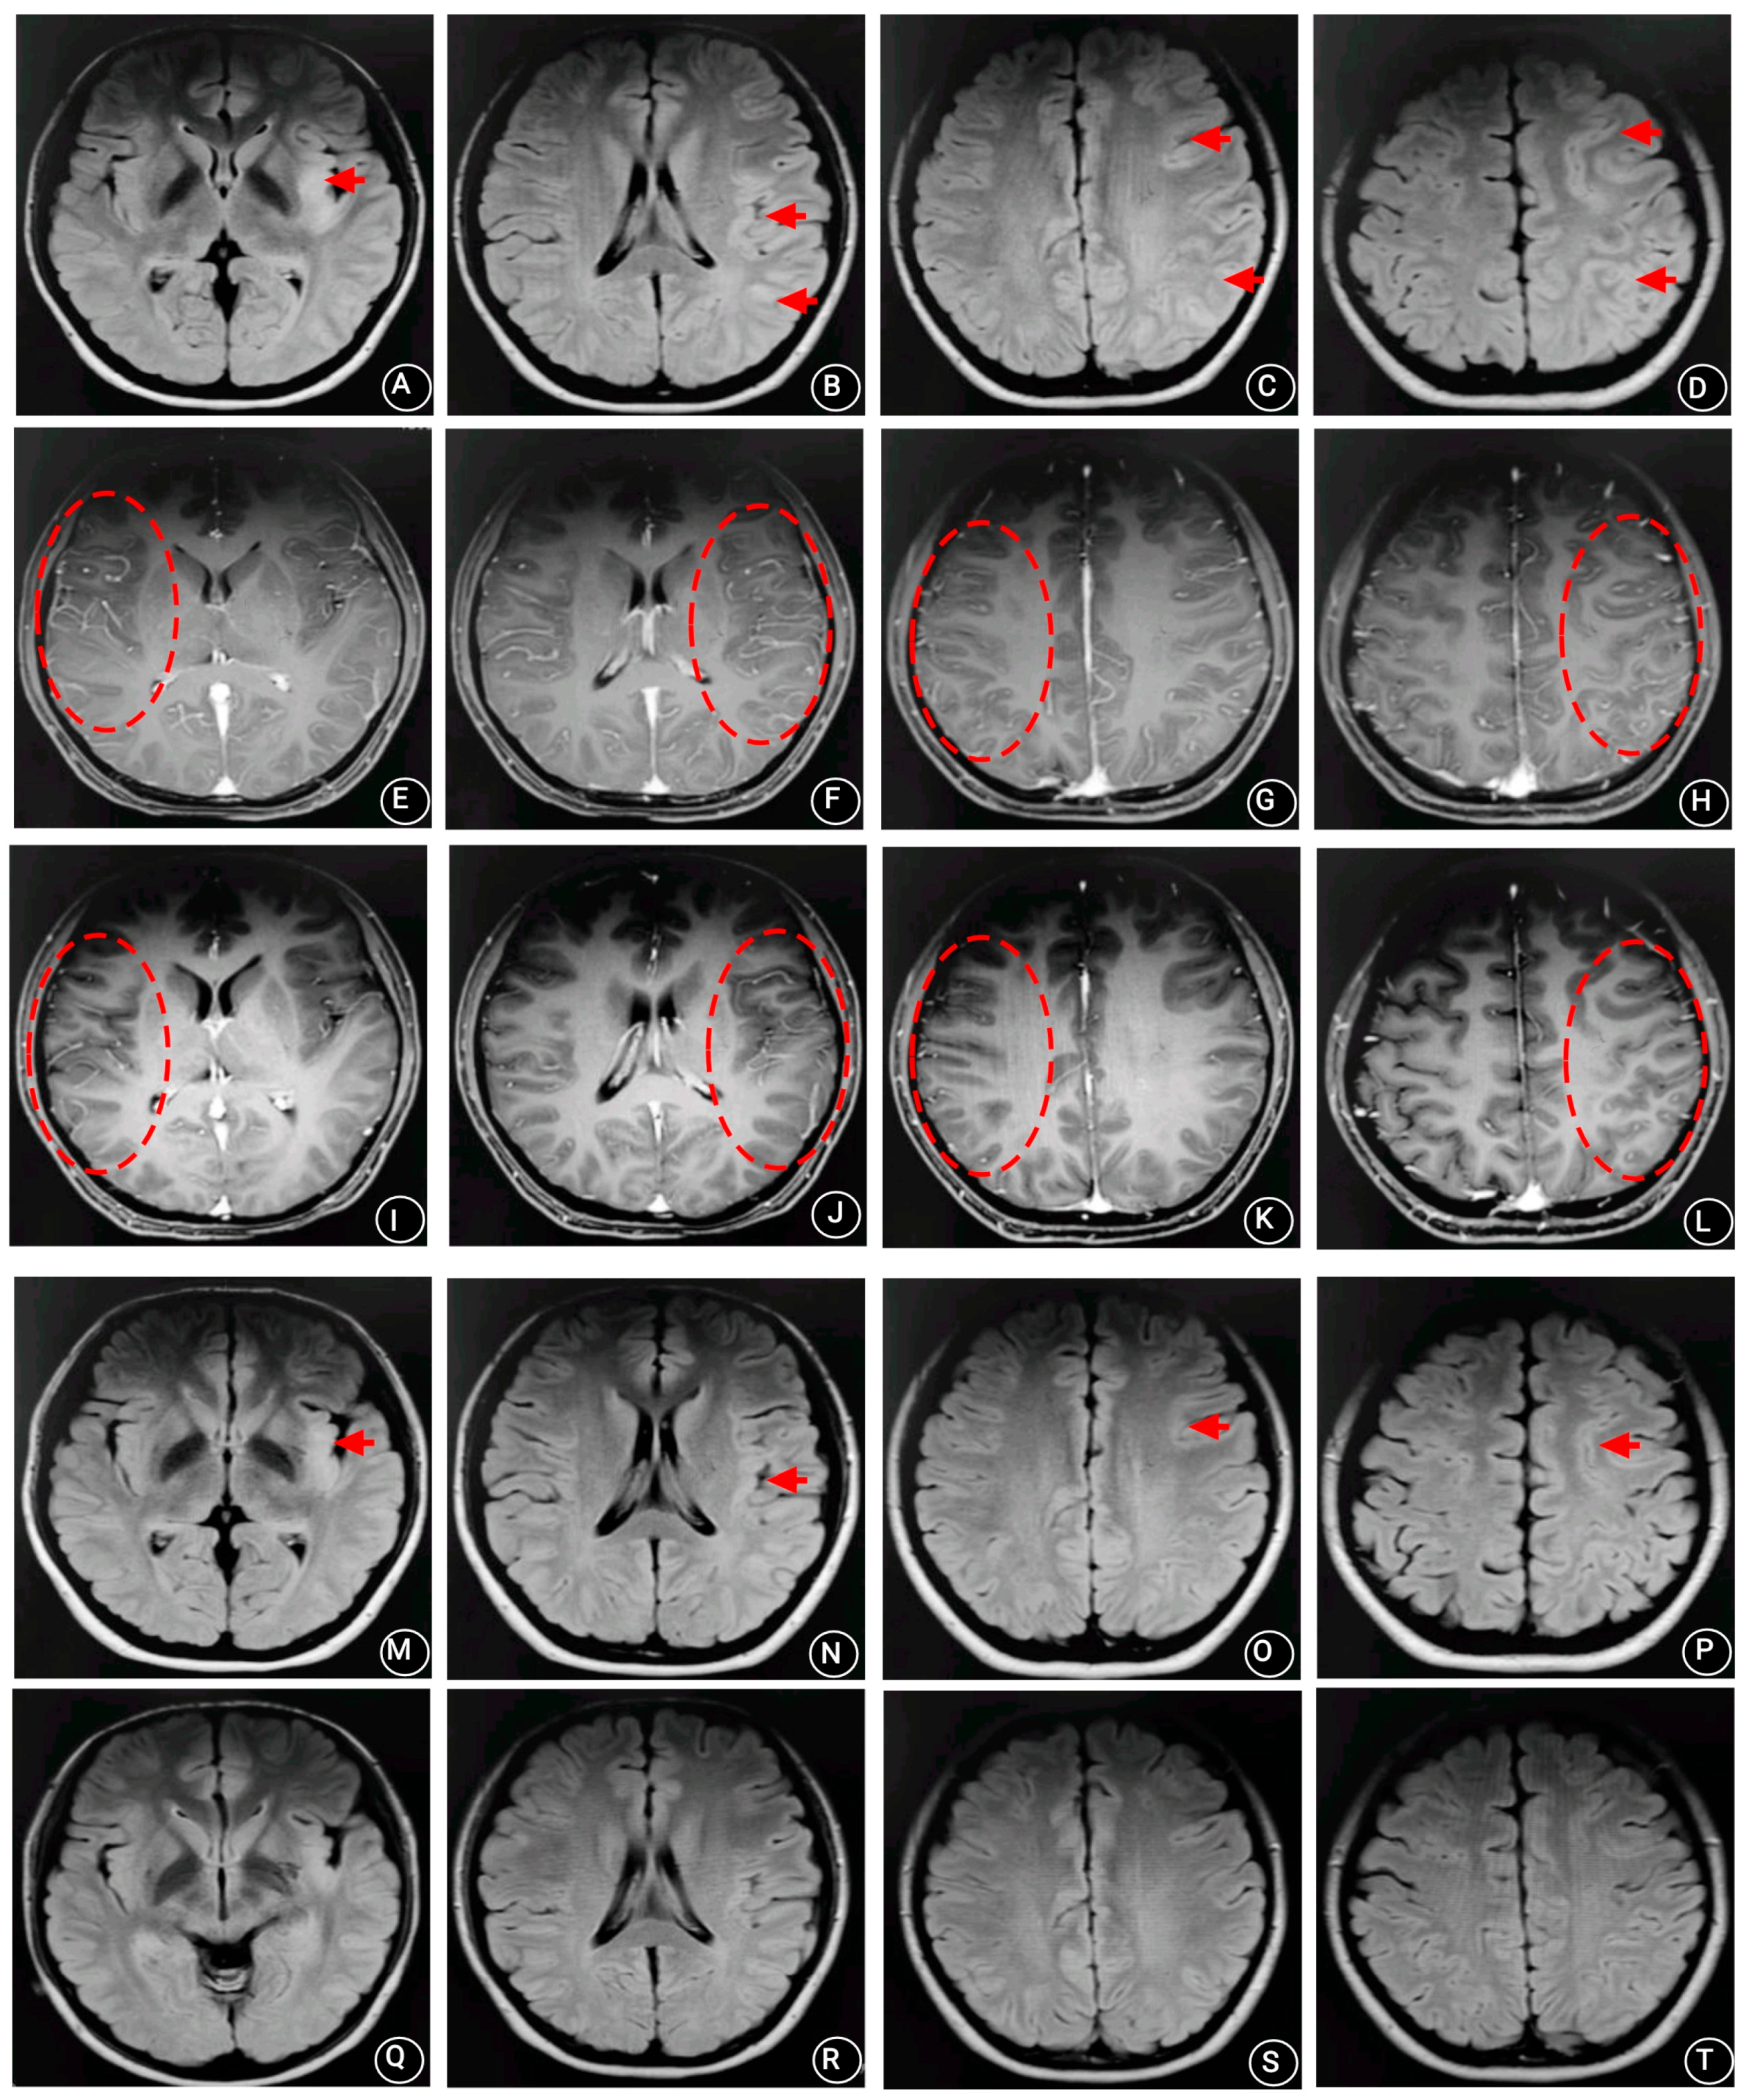

2. Case Presentation